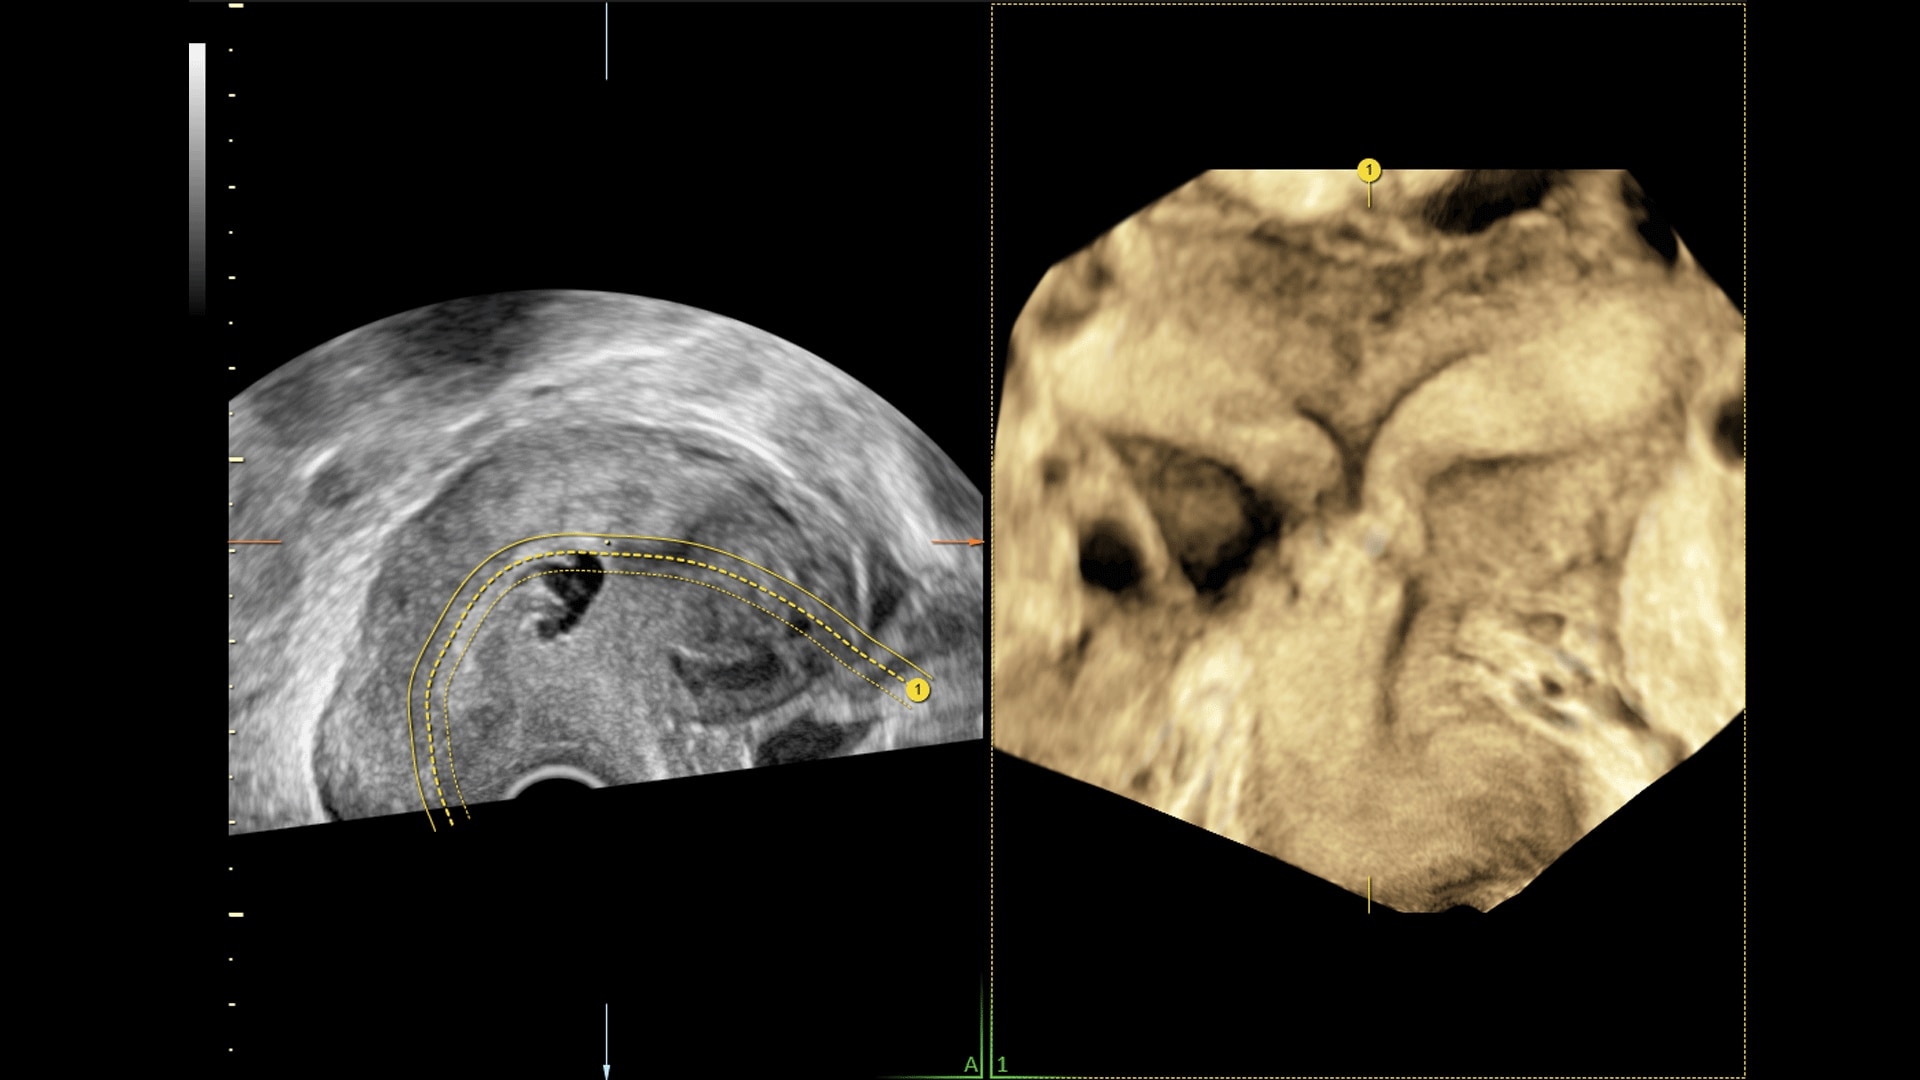

Generate spectacular 2D/3D and color Doppler images with increased penetration and stunning clarity, to help visualize critical details needed for diagnostic assurance. The Lyric Architecture unlocks new imaging and processing power to expand your imaging capabilities for years to come